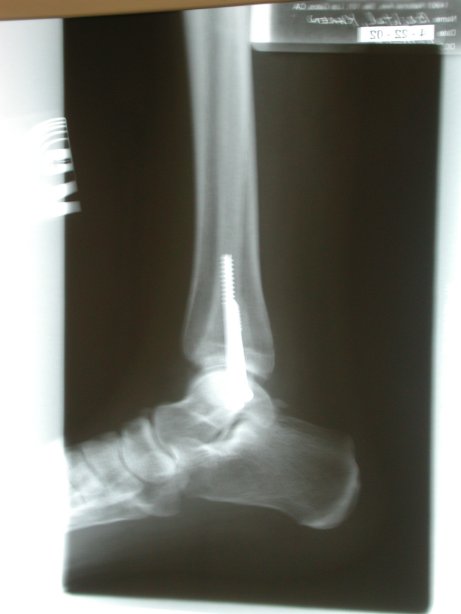

Updated X-Rays (1)

Updated X-Rays.